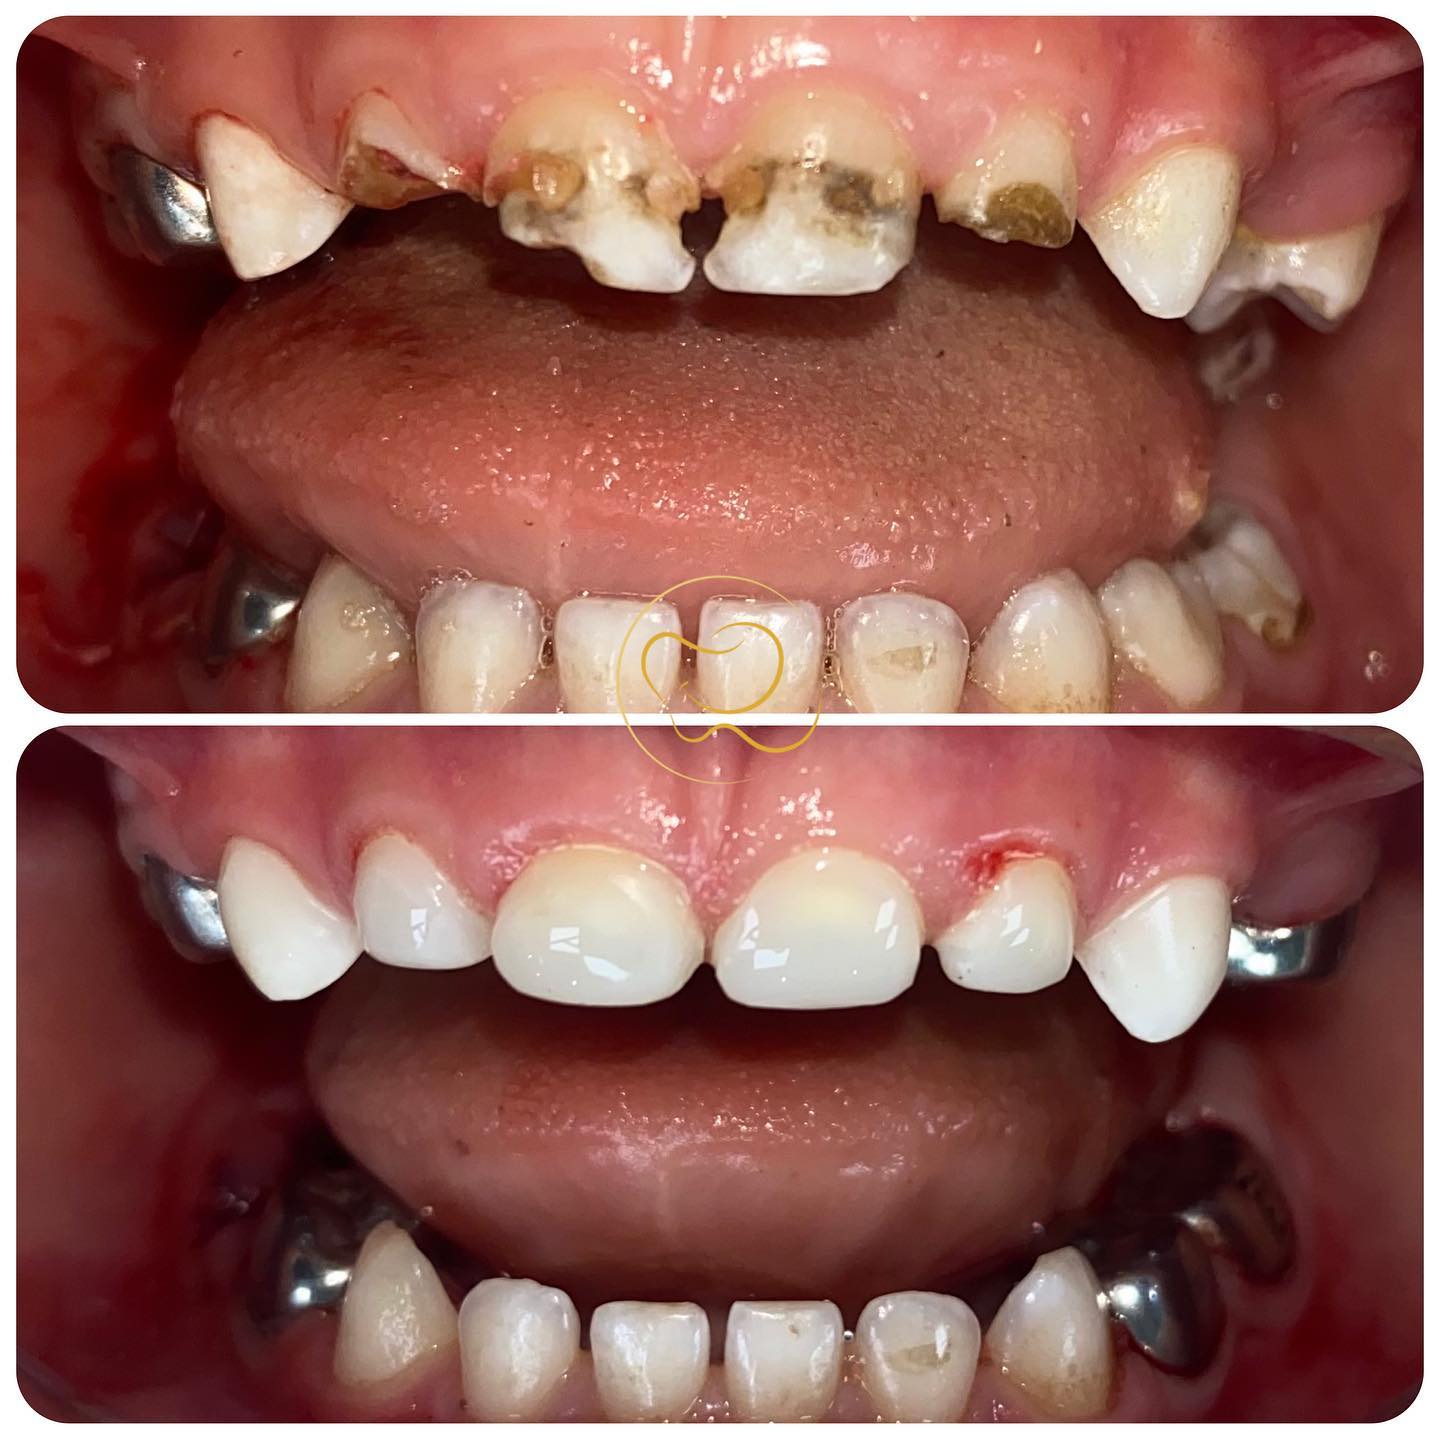

✨ علی قشنگم چشماشو بست و خوابید وقتی بیدار شد لبخندش دوست‌داشتنی‌تر شده بود. کاش میشد ما هم به همین راحتی چشمامونو ببندیم و وقتی باز کردیم ببینیم همه بچه‌های دنیا بدون ناراحتی و بیماری، دارن از ته دل میخندن..🧒👼 البته بیلدآپ دندونهای قدامی شیری تحت بیهوشی به این راحتی‌ها هم نیست و نیاز به رعایت چندین نکته تکنیکی داره که علاوه بر زیبایی، ماندگاری بلندمدت ترمیمهارو تامین کنه😉 #دندانپزشکی_کودکان #لبخند #کودک #دندانپزشکی